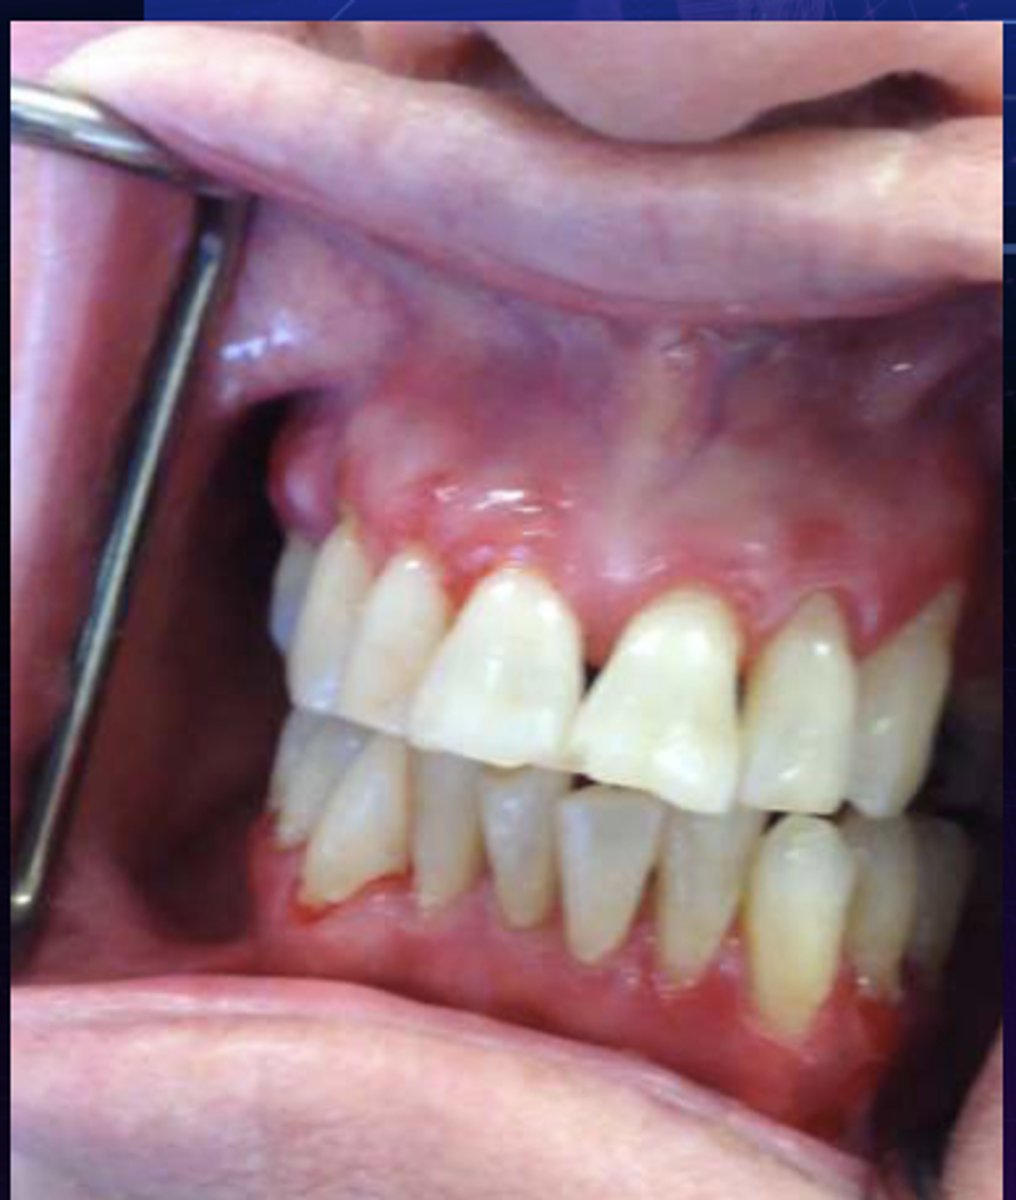

This is the clinical manifestation of which condition?

- Female predilection

- Diffuse, markedly erythematous gingiva

- Generally involves attached tissues

- Sensitivity to spicy foods

nikolsky sign: pressure to affected area with an object/compressed air → new vesicle formation or sloughing

What is a way to clinically diagnose desquamative gingivitis?

desquamative gingivitis

What condition?